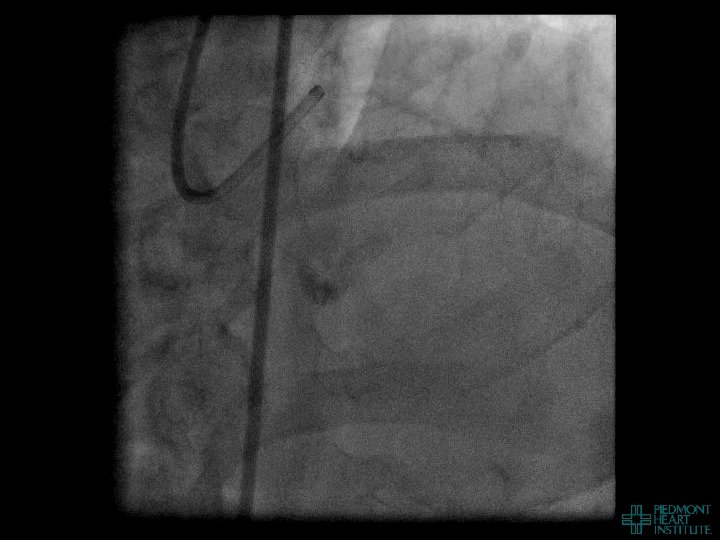

Case Example 2